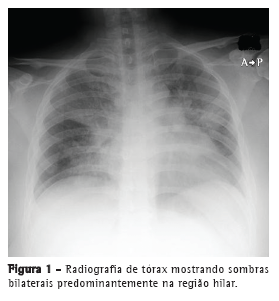

Relatamos um caso, tratado com sucesso, de pneumonia por VPI3 simulando pneumonia por influenza em uma paciente asmática de 31 anos de idade. A paciente apresentou febre alta (39.5°C), fadiga geral, dor articular sistêmica e anorexia durante dois dias antes de ser encaminhada a nosso centro médico. Era fumante e apresentava história de tabagismo (20 anos maço) e de asma brônquica (sem uso atual de medicação). A paciente também apresentava diabetes mellitus mal controlada e índice de massa corporal de 30 kg/m2. A radiografia de tórax revelou opacidades em vidro fosco difusas em ambos os pulmões (Figura 1). Exames laboratoriais revelaram reação inflamatória grave (proteína C reativa = 19,2 mg/dL e VHS = 83 mm/h). A paciente apresentou insuficiência respiratória grave e SpO2 de 80% em ar ambiente na primeira visita e passou a receber oxigenoterapia com ventilação não invasiva com pressão positiva. Devido à insuficiência respiratória grave, não foi realizada lavagem broncoalveolar. Embora o resultado de um teste rápido para detecção de antígeno de influenza tenha sido negativo, a paciente recebeu diagnóstico de pneumonia por influenza com base em sintomas semelhantes aos da gripe e em achados radiológicos, tais como opacidades difusas em vidro fosco (Figura 2).